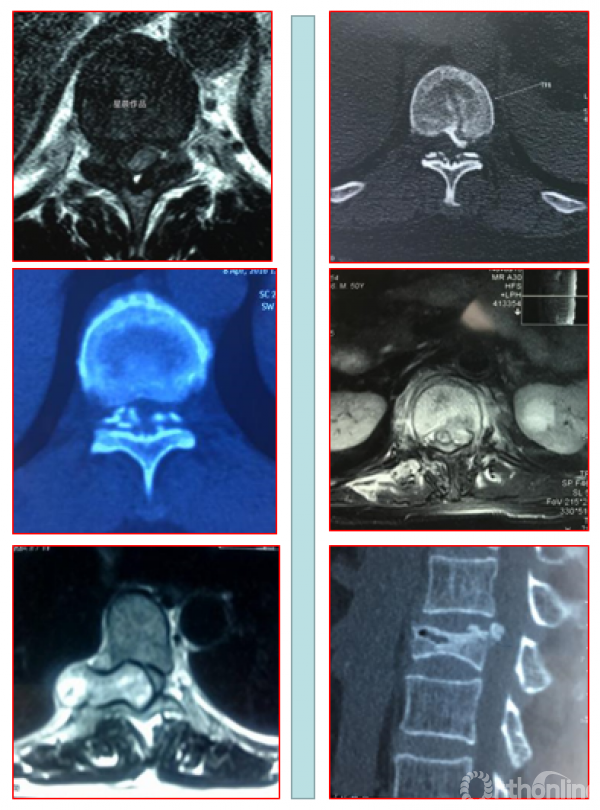

2. MRI分型:按照矢状位MRI分为圆弧形、鸟嘴型。

A.B.圆弧形(Round type);C.D.鸟嘴型(Beak type)

1. 按照矢状位CT分为线型、鸟嘴型、连续波形、连续圆柱形和混合型。

OPLL的CT矢状位分型为A.线性(Linear type);B.鸟嘴型(Beak type);C.连续波形(Continuous waveform type);D.连续圆柱形(Continuous cylindrical type)。混合型(Mixed type)为同时具有A-D两种及以上类型